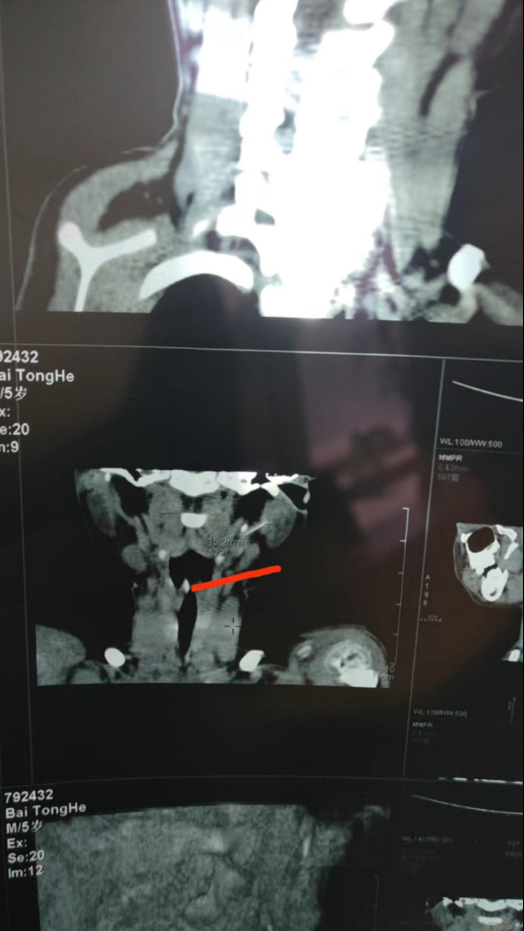

西安交通大学第一附属医院血管外科主任医师刘建林从业近40年,从病人的血管中取出过深静脉置管的导丝、造影导管、钢质针头和留置针导管,他评价,留置针导管是最难取的。“异物越短、越细小、越不显眼,取出难度就越高。金属材质容易通过医学影像定位,但是塑料材质的留置针导管不透X射线,有一定几率会出现导管找不到的情况。”

▲B超下留置针导管细小的显影。受访者供图